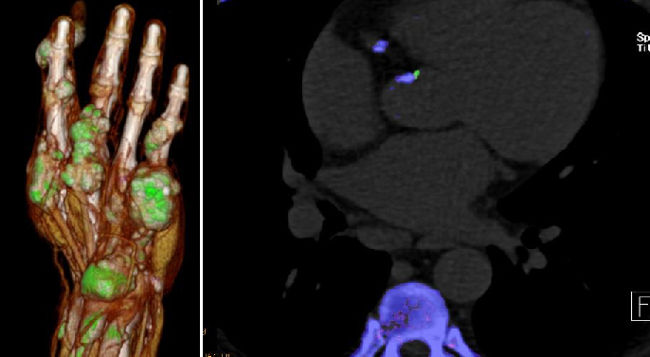

- Dual-energy CT (DECT) in gout: comparison with US, findings in extra-articular regions and cardio in gout and subgroup patients

- X-ray in comparison with DECT in gout patients

- X-ray in comparison with US in erosion assessment

Musculoskeletal Imaging

- Klauser AS, Halpern EJ, Strobl S, Gruber J, Feuchtner G, Bellmann-Weiler R, Weiss G, Stofferin H, Jaschke W.: Dual-Energy Computed Tomography Detection of Cardiovascular Monosodium Urate Deposits in Patients With Gout. JAMA Cardiol. 2019 Oct 1;4(10):1019-1028.

- Strobl S, Kremser C, Taljanovic M, Gruber J, Stofferin H, Bellmann-Weiler R, Klauser AS.: Impact of Dual-Energy CT Postprocessing Protocol for the Detection of Gouty Arthritis and Quantification of Tophi in Patients Presenting With Podagra: Comparison With Ultrasound. AJR Am J Roentgenol. 2019 Dec;213(6):1315-1323.